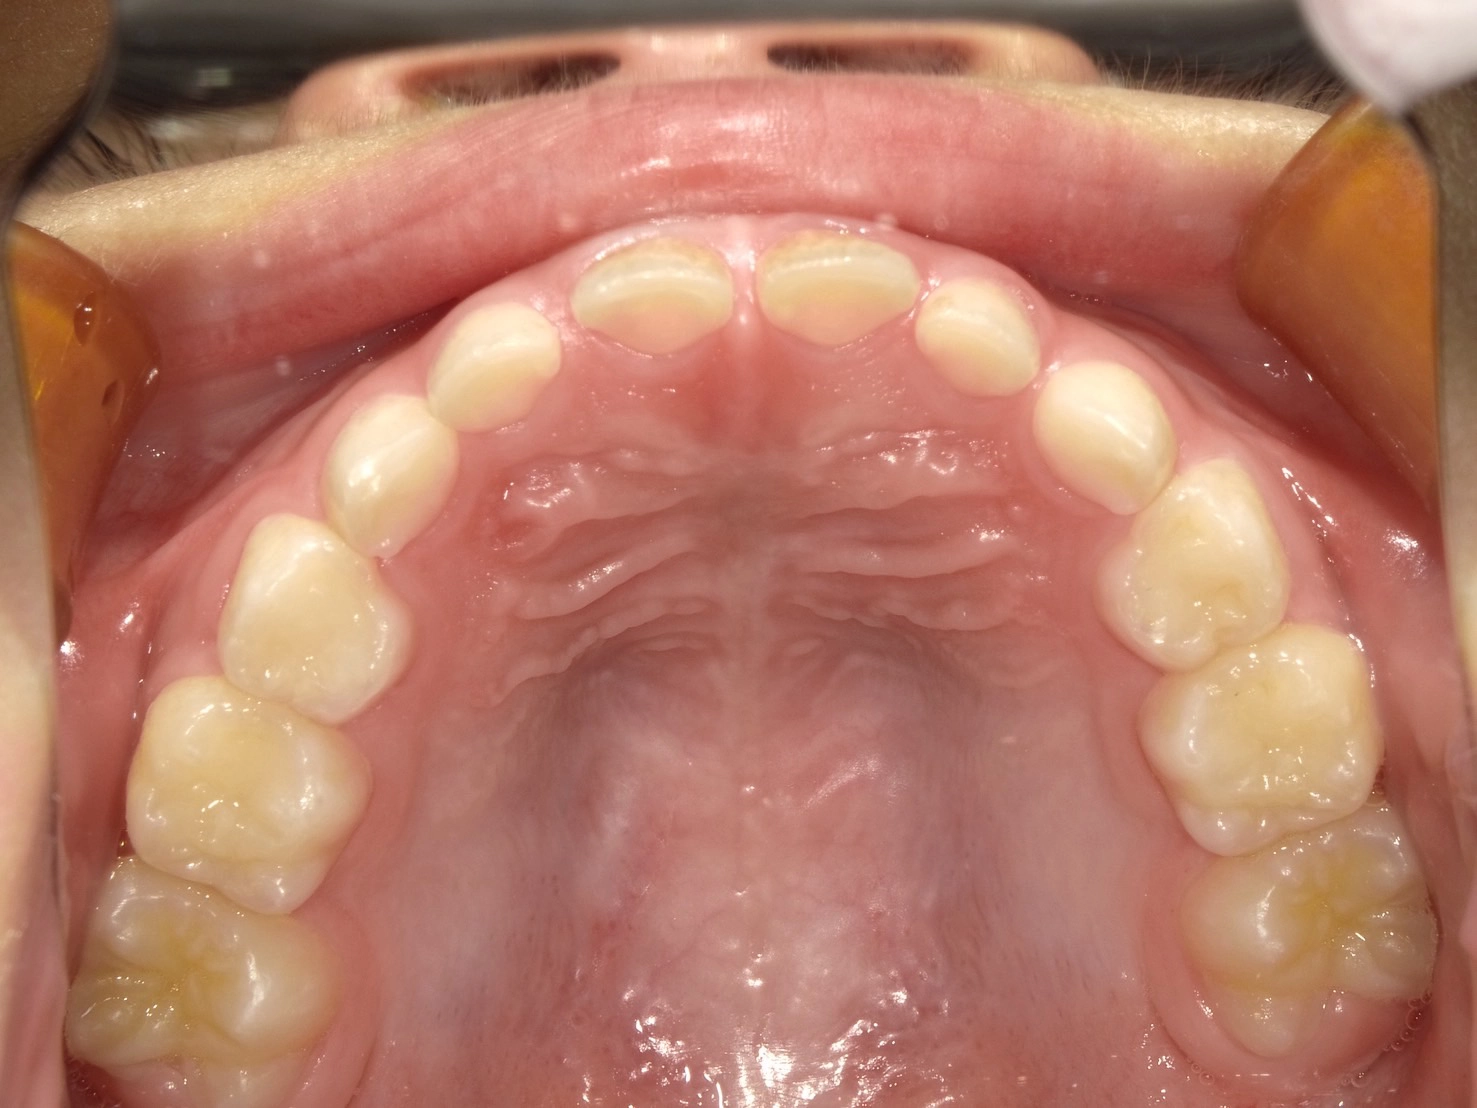

実際に小野歯科医院で行っているマイオブレースを用いた小児矯正の症例を紹介します。

どんどんきれいな歯並びになっていく様子を一緒に確認していきましょう!

治療前

術名 | マイオブレース矯正 |

---|---|

年齢 | 6歳 |

性別 | 男性 |

主訴 | 下の前歯のガタつきが気になる |

診断名 | 叢生 |

治療内容 | マイオブレース矯正 |

治療期間 | 治療開始2ヶ月時点での変化 |

費用 | 基本料33万(検査診断料.月々の調整料別途) |

リスク・副作用 | 特になし |